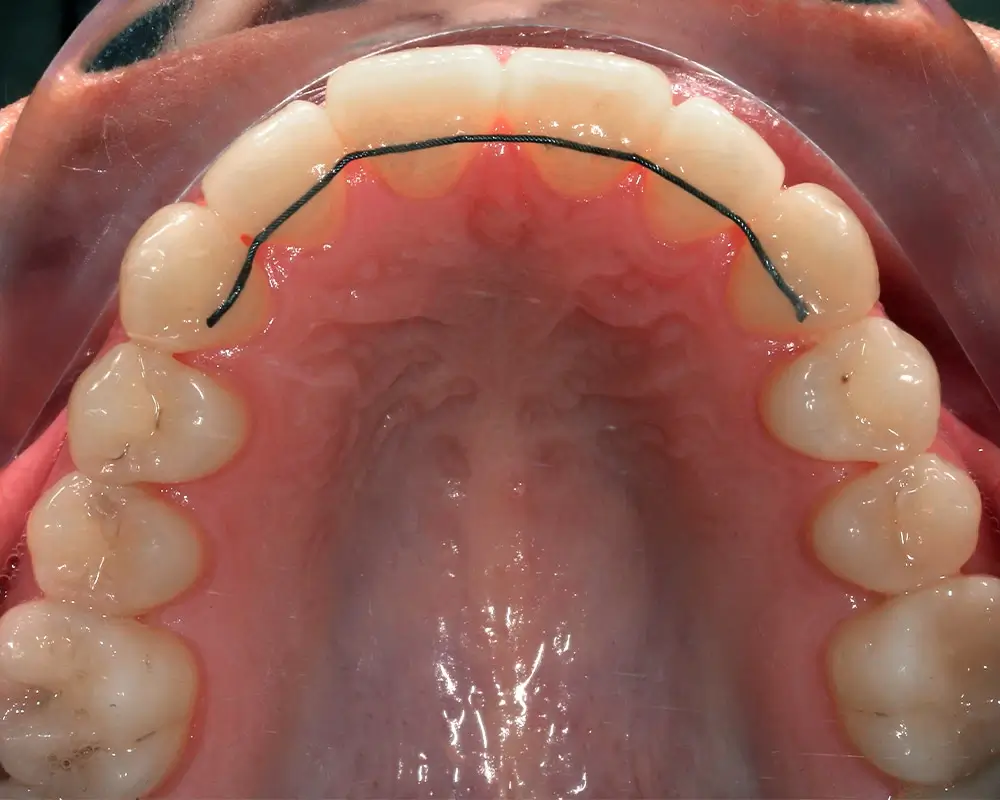

Эффективность устранения дефекта прикуса посредством элайнеров FlexiLigner.

Результаты лечения

ПОСЛЕ